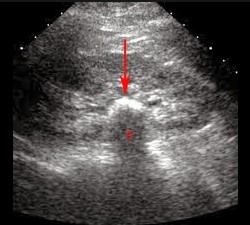

Siêu âm

Khi nghi ngờ có thận có sỏi, phương pháp chẩn đoán đầu tiên được chỉ định là siêu âm, vì nó khá hiệu quả, đơn giản và ít tốt kém. Khi siêu âm, bác sĩ có thể phát hiện sỏi, đồng thời có thể tiên lượng được mức độ ứ nước của thận, niệu quản và độ dày mỏng của chủ mô thận.

Một số trường hợp bị sỏi nhưng không có biến chứng hoặc triệu chứng rõ ràng, đã được phát hiện ra khi tình cờ khám siêu âm vì một lý do nào đó khác hoặc trong các cuộc thăm khám tổng quát định kỳ.